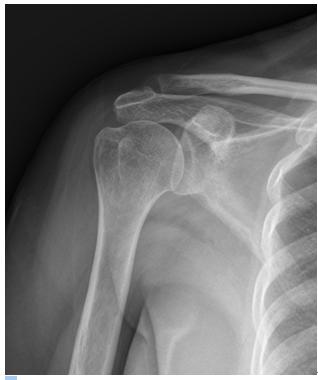

급성 탈구인 경우 진찰소견과 엑스레이 소견을 보고 탈구의 방향을 조사하는데 대부분의 경우 팔이 앞쪽으로 빠지는 전방 탈구입니다. 재발성 탈구가 되면 MRI 등으로 관절순 또는 인대들의 상태를 분석하는 것이 필요합니다. 또한 재발성 탈구시 골절을 동반하는 경우와 골결손이 심하면 수술전 CT사진이 필요합니다.